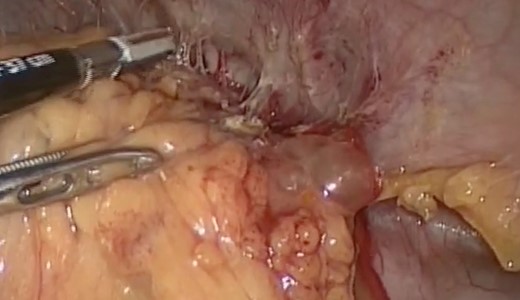

Intraoperative findings included extensive inflammation involving the inferior half of the spleen, the splenic flexure of the colon and the distal pancreas, as well as the abscess in question which contained approximately 10 cc of purulent material (Figs 3 and 4). The final surgical specimen included the entire spleen and the histologic report of pancreatic tissue compromised by the abscess. The patient was transferred to the surgical ICU for 24 hours. The following day, the blood cultures taken on admission grew an extended spectrum beta-lactamase producing Escherichia coli resistant to carbanemic agents and sensitive to tigecycline. The antibiotic regimen was modified accordingly, and after 7 days the patient was discharged symptom-free and with a plan to complete 15 days of tigecycline at home.

Splenic mass, inflammatory adherences from the major momentum to the spleen, colon and diaphragm.